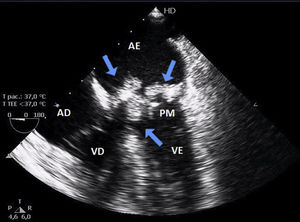

Laboratory tests showed slight leukocytosis without eosinophilia. Transthoracic echocardiography revealed an image suggesting vegetations on the biological valve, which was confirmed by transesophageal echocardiography (Figure 1). Blood cultures were taken and empirical antimicrobial therapy was begun, but the patient’s infection worsened and he developed hemodynamic instability. The mitral bioprosthesis was accordingly replaced by a metal valve. The vegetation adhering to the bioprosthesis was cultured and following macroscopic examination (Figure 2) amphotericin B was added. On the sixth postoperative day growth of T. beigelii was observed in the culture from the bioprosthesis and, in view of clinical deterioration, the antifungal was replaced by voriconazole. However, the patient developed multiorgan failure and died on the 13th day after surgical intervention.